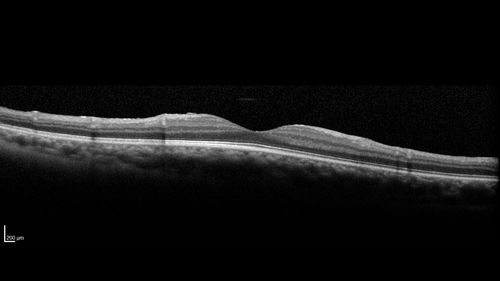

20 year old mane with fresh vitreous hemorrhage in the right eye.  At age 15 he had a PPV and laser in the left eye and laser in the right eye.  The vision is OD 20/80 PH 20/25, OS 20/25.  The left eye has a mild cataract.  He had prior testing for coagulopathies which was negative.  Testing done for syphillis and TB was negative.  Additional laser was done to prevent further bleeding in the right eye.

Eales Disease and fresh vitreous hemorrhage - 20 year old man